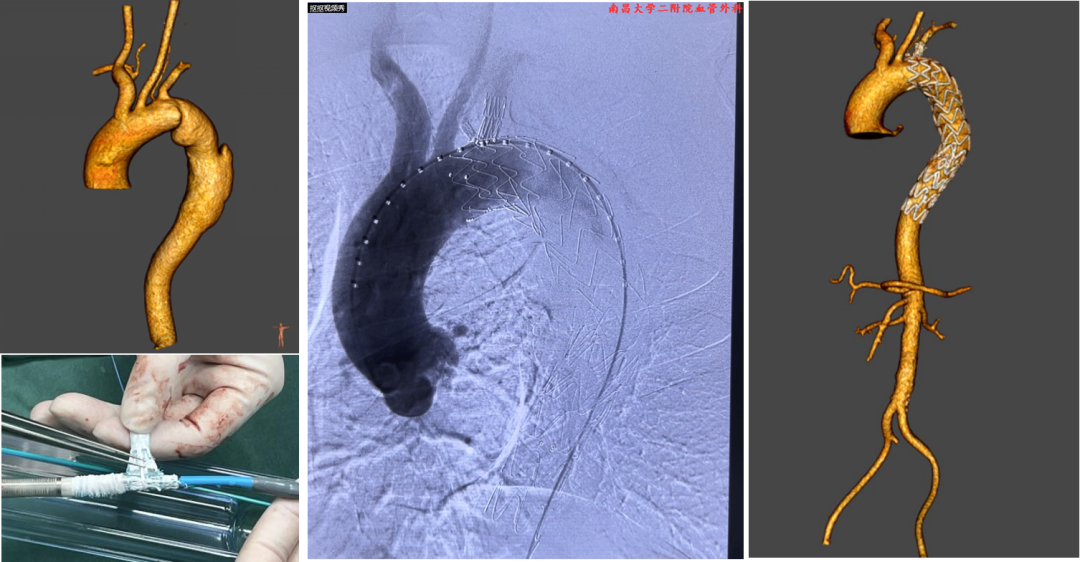

【分支支架开窗技术】未来趋势的探索

分支支架是指自带弓上分支的主动脉覆膜支架,尤其是三分支支架的使用促进了全腔内修复术的重大进展。

Castor支架是目前国内唯一上市的分支支架产品,研究表明术后长达92个月随访,并发症发生率为0.035%。可结合左锁骨下动脉开窗技术,也可重建左颈总动脉血运,适用于Z2和Z3区病变。

临床应用:医源性夹层:Castor分支支架+迷走右锁骨下动脉原位开窗(需90度角度配合特殊导丝完成)

逆撕A型夹层:Castor分支支架联合迷走左椎动脉预开窗。

弓部动脉瘤:Castor联合内嵌分支LSA预开窗术,目的为防内漏

避免转流的复杂病例:Castor+原位及预开窗(免转流三开窗)治疗弓部动脉瘤